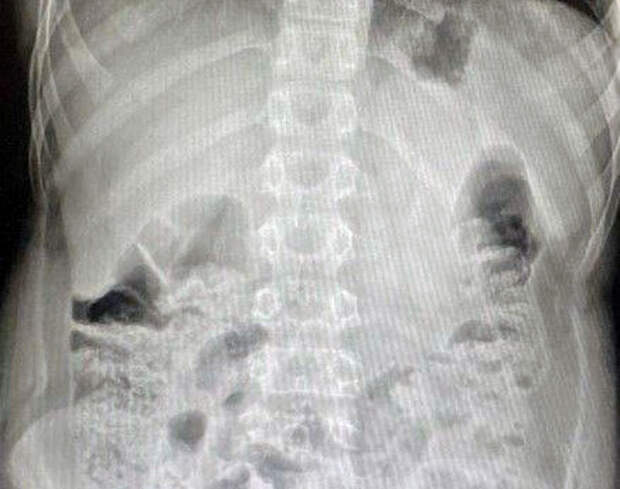

Между моментом инцидента и обращением за помощью прошло очень мало времени. За это время инородное тело успело опуститься в слепую кишку. Врачи приняли решение о немедленном извлечении предмета."Вначале выполнили лапароскопию, чтобы визуализировать как возможные осложнения, так и расположение инородного предмета. Затем провели эндоскопическое исследование, во время которого с помощью специальной петли извлекли литиевую батарейку", - поделился детский хирург, заведующий хирургическим отделением №1 Игорь Хворостов.

Врач добавил, что батарейка не успела окислиться, так что химического ожога удалось избежать. Мальчика выписали домой через два дня, как подчеркнули специалисты, полностью здоровым.